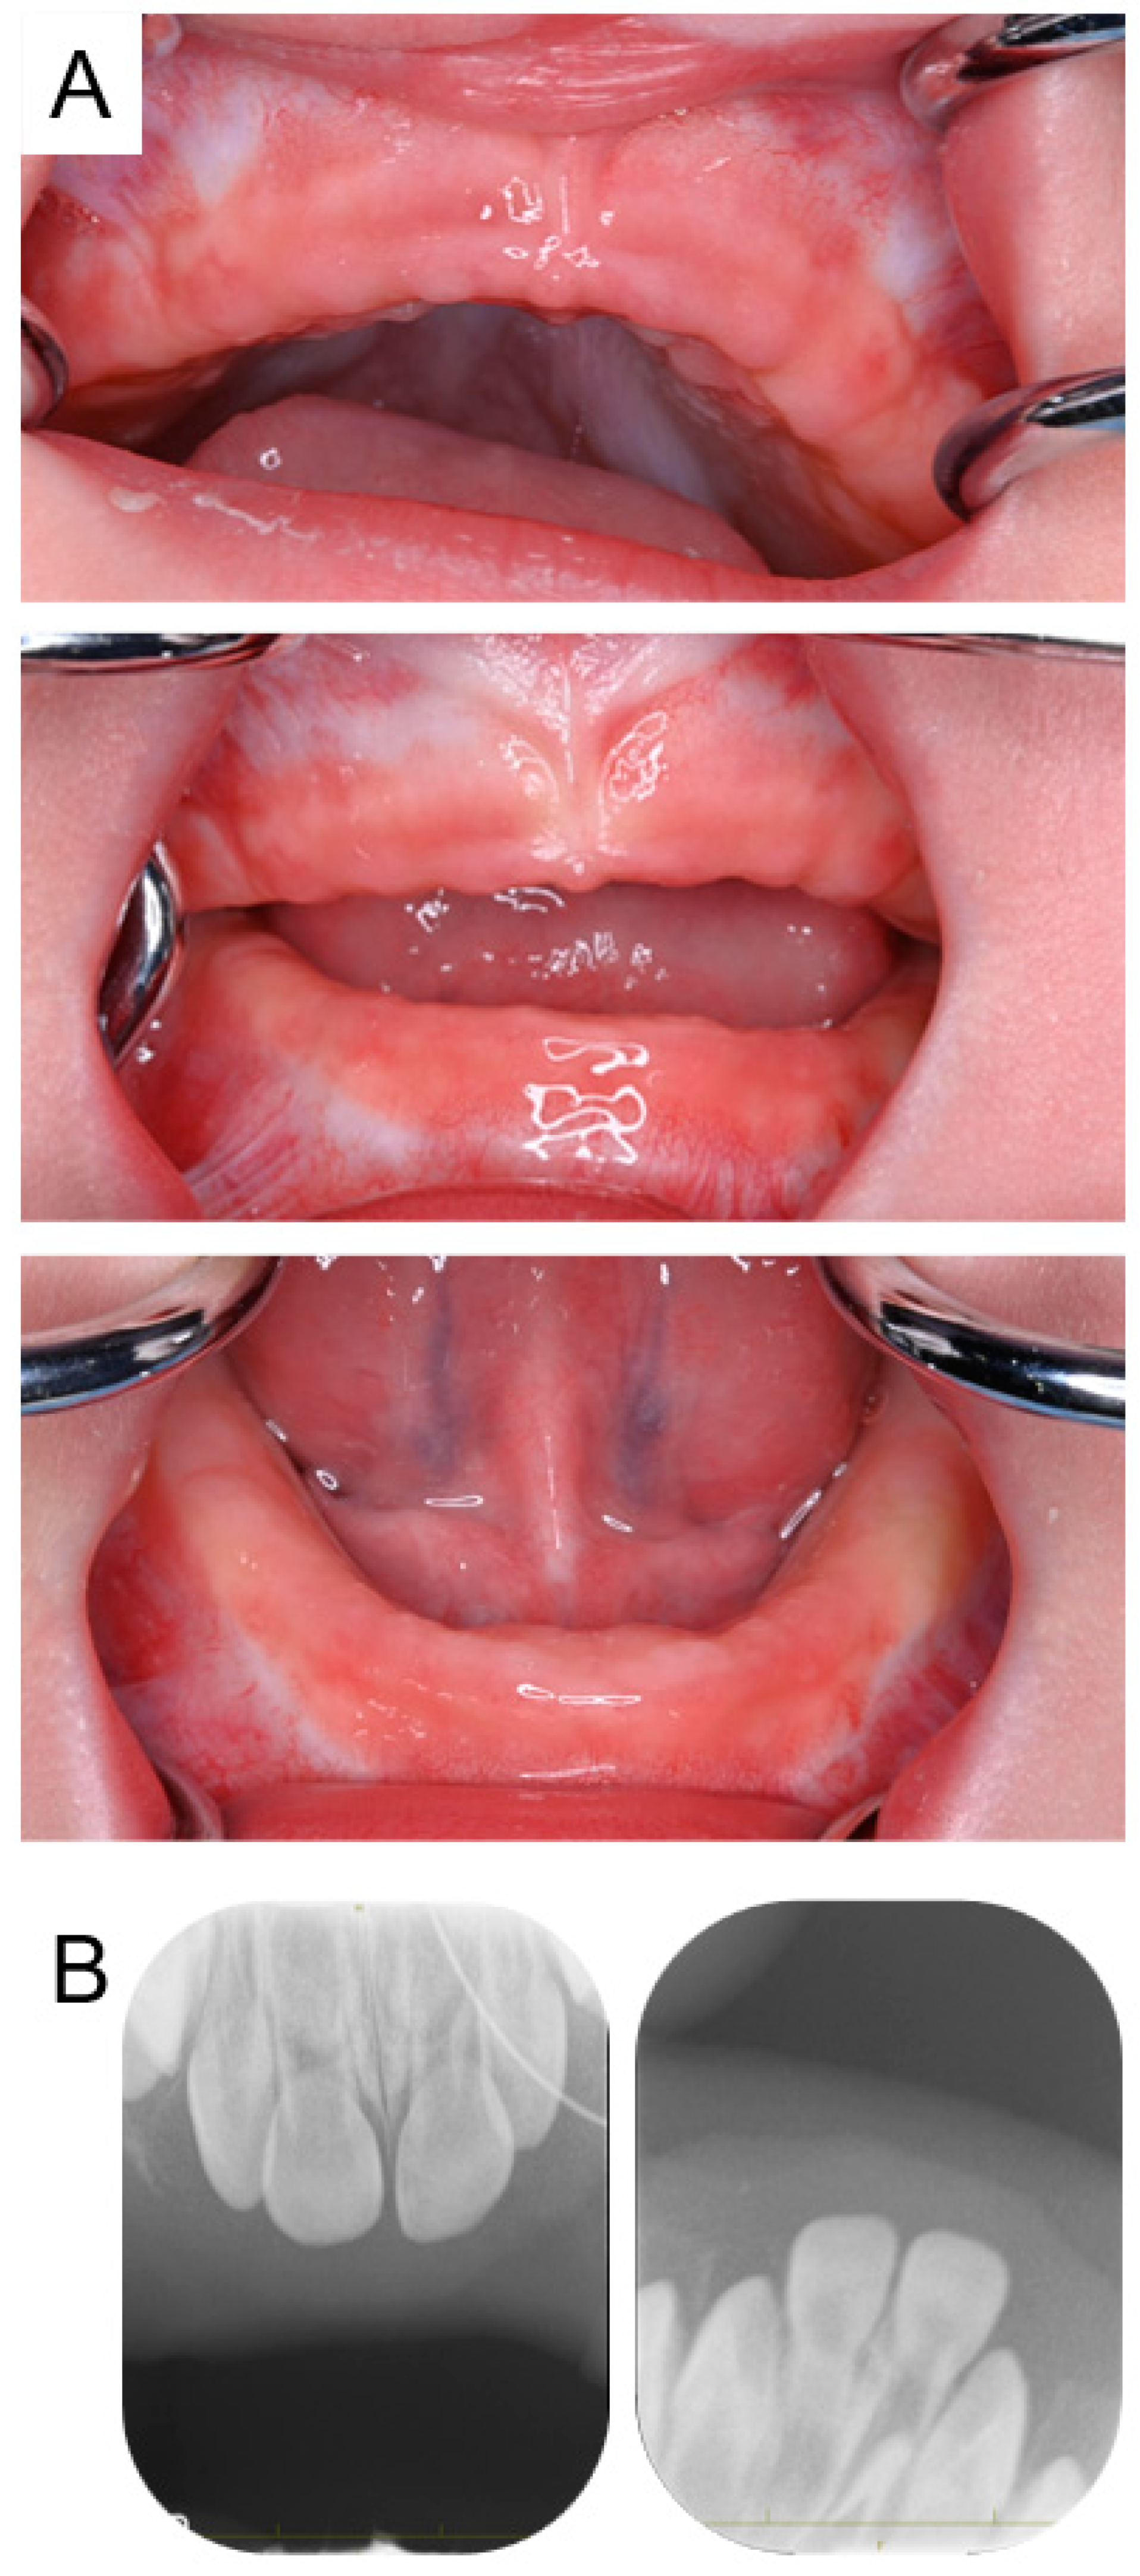

2.1. Case 1

2.2. Case 2